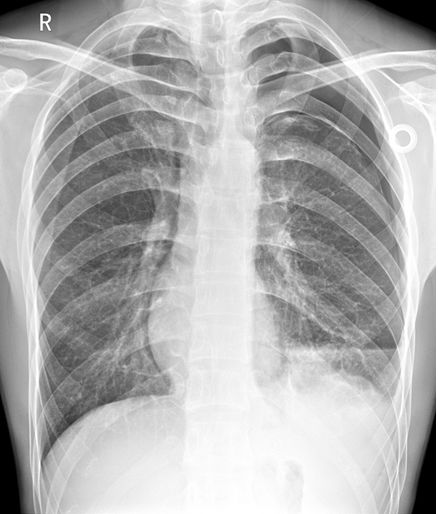

病例3患者的X线胸片

右上肺野见异常透亮无肺纹理区,内缘可见发线状肺组织压缩边缘,肺叶被压缩约30%(蓝色箭头)。心影及纵隔向对侧轻度移位(蓝色直线)。两膈面光滑,肋膈角锋利。